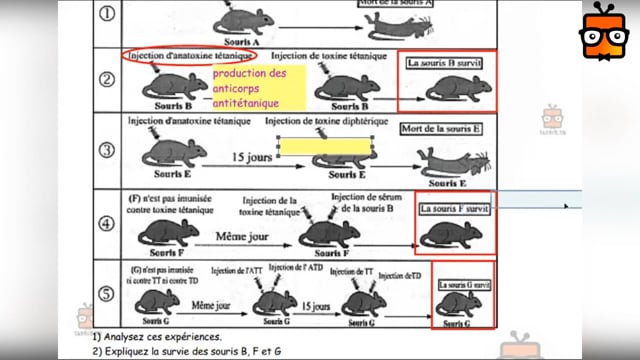

Sciences SVT

1ᴱ̀ᴿᴱ année